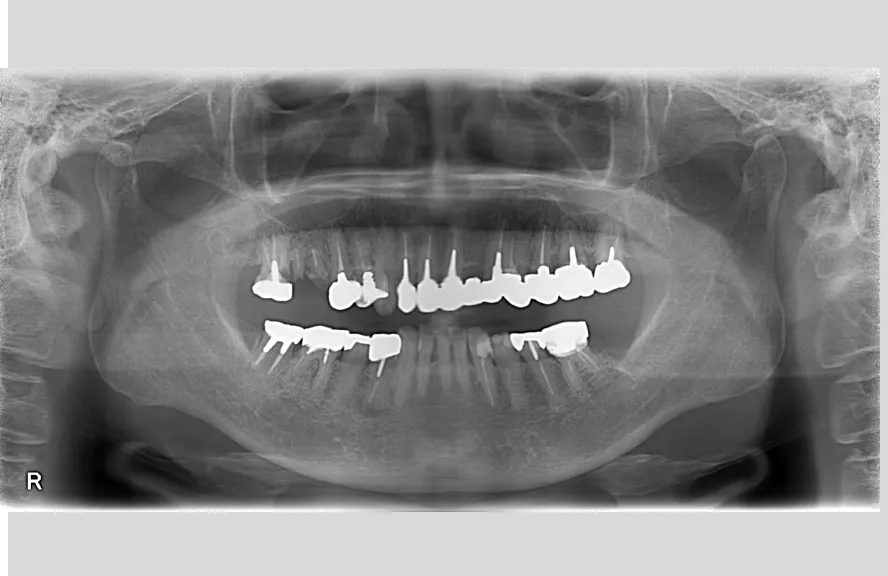

骨格の前後的な差がある方でした。術前のレントゲンより、上下で歯牙の損傷に明らかな差があるのがみてとれます。

既にインプラント治療がなされており、使えるインプラントを使いながら足りないところにインプラントフィクスチャーを埋入し、噛み合わせを再構築する必要がある方でした。

上の前歯、右上の奥歯のインプラントはもう既に使える状態ではなく、また年月を経てすり減ってしまった下の前歯は噛み合わせを再構築する上で利用が難しい状況でした。

レントゲンをよく見るとお分かりいただけるかと思いますが右下の奥歯のインプラント(レントゲンでは左右逆にうつるので、左下)が既にインプラント周囲炎になっていました。

本当に治療をやり切ってしまうなら、右下の奥2本のインプラントを抜去、新しいインプラントフィクスチャーを埋入すべき症例でした。

しかし、患者さんとの話し合いで、「まだ使えるインプラントは置いておこう」ということになり、右下のインプラントは置いたまま治療を行っています。今後の人生の中で腫れたり痛む可能性があることは重々ご承知いただいております。

複数のインプラントフィクスチャーの埋入においては埋入位置がずれると後々のクラウン製作に難が生じます。そのリスクを最低限にするため、ガイデッドサージェリーを行っております。